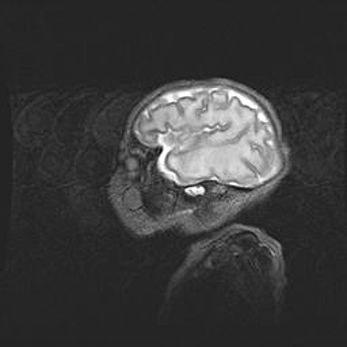

Лейкомаляция с кистозно-глиозной дегенерацией головного мозга.

Возраст: 2 месяца 25 дней

Вес: 6400 г

Окружность головы: 40 см

Срок гестации: 41 неделя

Лейкомаляцию относят к ишемически-гипоксическим повреждениям головного мозга, диагностируемым у новорожденных. При лейкомаляции в головном мозге обнаруживают очаги некроза, возникшие после тяжелой гипоксии и нарушения кровотока. В процессе морфогенеза очаги проходят три стадии: 1) развития некроза, 2) резорбции и 3) формирования глиозного рубца или кисты. Перивентрикулярная лейкомаляция (ПЛ) встречается примерно в 12% случаев среди новорожденных, обычно – у недоношенных детей, причем, частота ее зависит от массы, с которой младенец появился на свет. Наибольшее число малышей страдает лейкомаляцией, если масса при рождении 1500-2500 г.